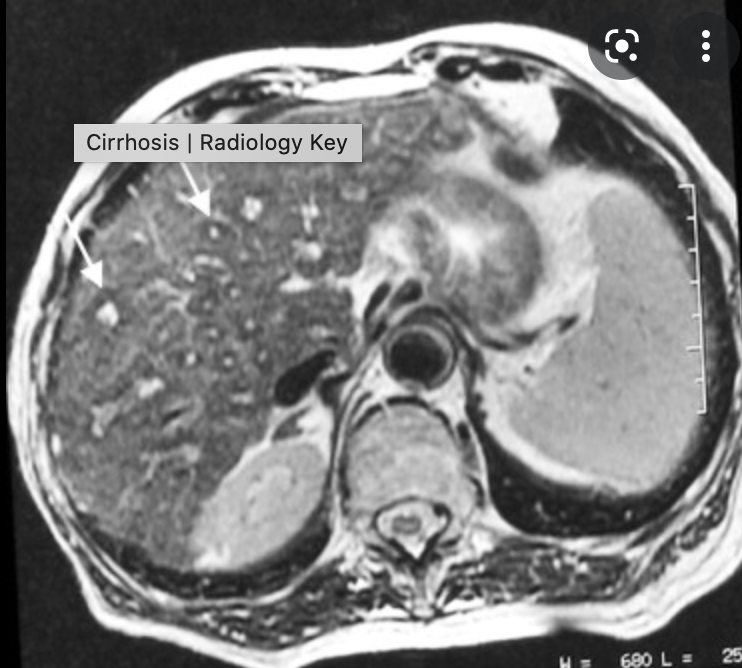

- KLATSKIN TUMOUR (image)

- Cholangiocarcinoma

- adenocarcinoma of the biliary tree

- Two types

- scirrhous type

- worse prognosis

- Polypoid type

- scirrhous type